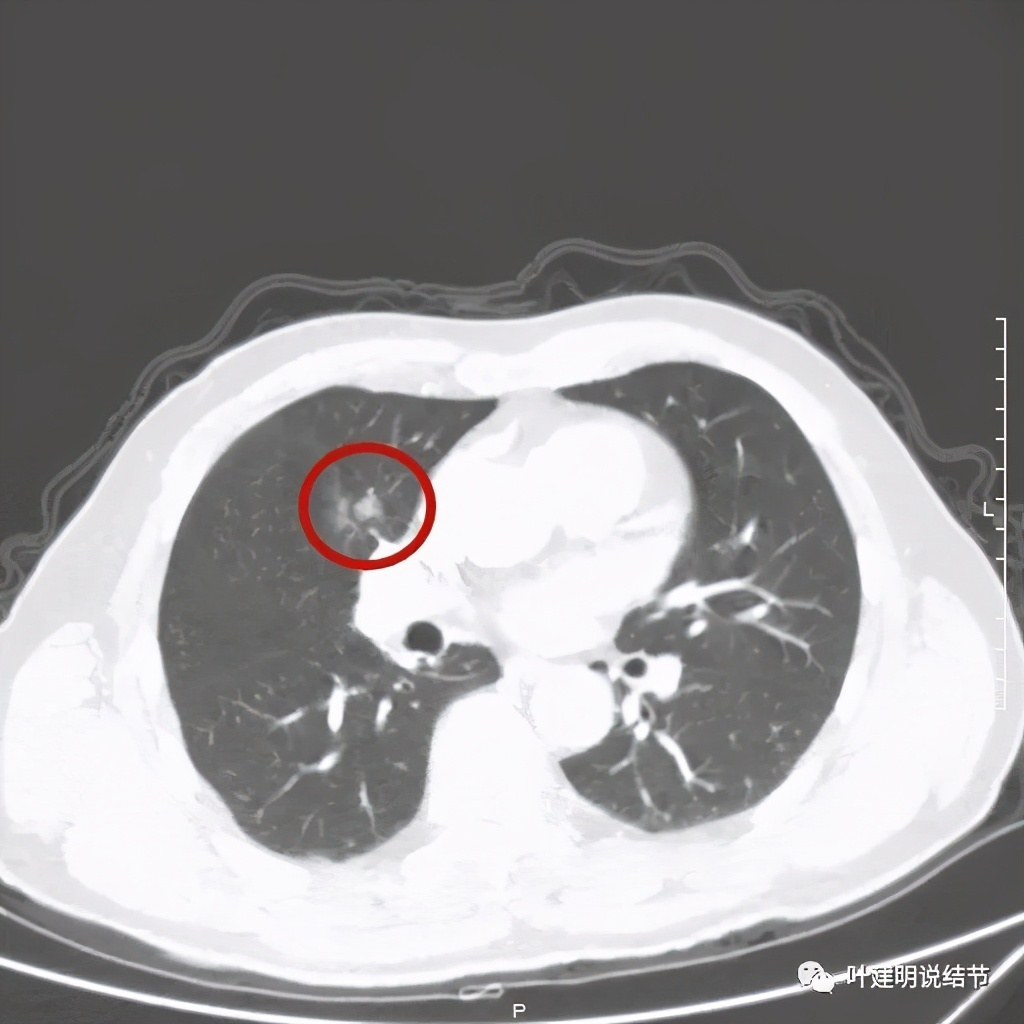

病灶有分叶及胸膜牵拉

以上几图示病灶膨胀感明显,无卫星灶,周围无渗出性改变